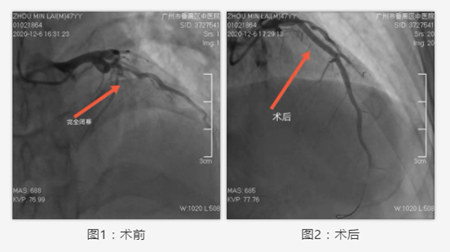

鉴于手术风险极大,祁家祥主任带领其团队沉着应对、高效配合,制定详细手术方案,为患者迅速完成桡动脉穿刺,实施急诊冠状动脉造影。术中,冠脉造影显示患者巨大的前降支自近端完全闭塞,祁家祥主任凭借着丰富的操作经验,精湛的医疗技术,果断送入指引导管及导丝入左冠脉前降支,导丝通过闭塞血管,送入球囊在闭塞地段进行扩张,闭塞的前降支打通。随后,迅速在患者闭塞的血管内植入支架。随着患者血流的完全再通,大家紧绷的神经才有所放松。手术顺利完成,患者生命得到挽救。